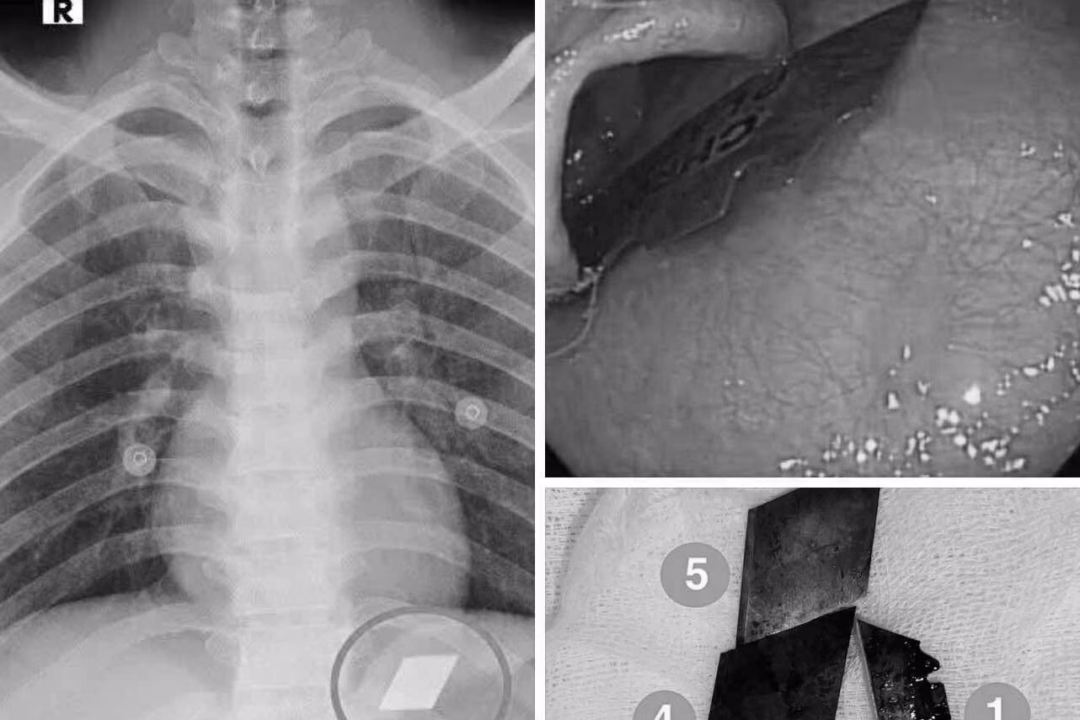

Ngày 10/7, Khoa Hồi sức cấp cứu – Bệnh viện Đa khoa Bình Dương đã tiếp nhận một trường hợp cấp cứu hiếm gặp. Bệnh nhân P.V.L, 26 tuổi, được nhập viện trong tình trạng nuốt nhiều dị vật kim loại sắc nhọn, bao gồm dao rọc giấy và dao lam.

Qua thăm khám và chụp X-quang, các bác sĩ đã phát hiện các dị vật cản quang tại vị trí dạ dày. Bệnh nhân ngay lập tức được chỉ định nội soi cấp cứu để gắp bỏ dị vật. Dưới sự phối hợp chặt chẽ giữa ê-kíp nội soi và gây mê, các bác sĩ đã thành công gắp 4 lưỡi dao rọc giấy ra khỏi dạ dày và một phần lưỡi dao lam mắc tại vùng hạ họng – miệng thực quản.

Sau thủ thuật, bệnh nhân được theo dõi sát và đã ổn định sức khỏe, xuất viện trong tình trạng an toàn. Theo bác sĩ Phan Lê Quốc Du, Khoa Thăm dò chức năng, Bệnh viện Đa khoa Bình Dương, các dị vật sắc nhọn trong đường tiêu hóa đòi hỏi phải can thiệp nội soi kịp thời. Nếu không lấy ra kịp thời, dị vật có thể gây thủng thực quản, thủng ruột, dẫn đến biến chứng nặng nề, thậm chí tử vong.